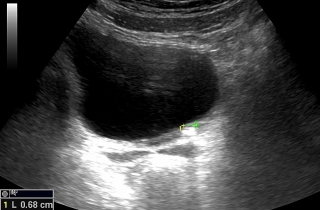

Kamica nerkowa

Kamica to jedno z częstszych schorzeń układu moczowego. Kamień, który wydostanie się z nerki i utknie w moczowodzie blokuje odpływ moczu powodując tzw. wodonercze oraz kolkę nerkową. W #KlinikaBulwarDedala leczymy kolki nerkowe.